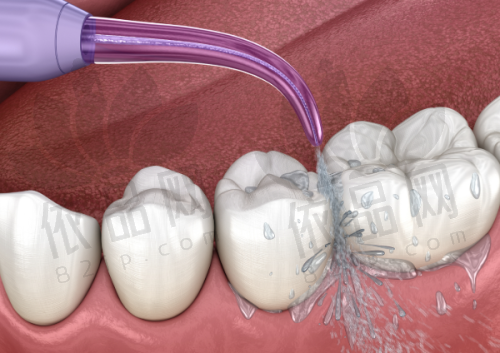

罗春雨医生在实际操作中善于运用现代口腔治疗设备,通过微痛技术、冷热感应等方式,降低患者在治疗过程中的不适。他擅长在确保治疗成效的同时,尽较大努力让患者获得良好的就医体验。

此外,罗医生在根管治疗领域也不断更新操作手法,通过显微辅助操作等方式提高手术成功几率,减少治疗后的复发概率。对患有复杂病灶的患者,他也能从多项技术角度提供细致的治疗计划。